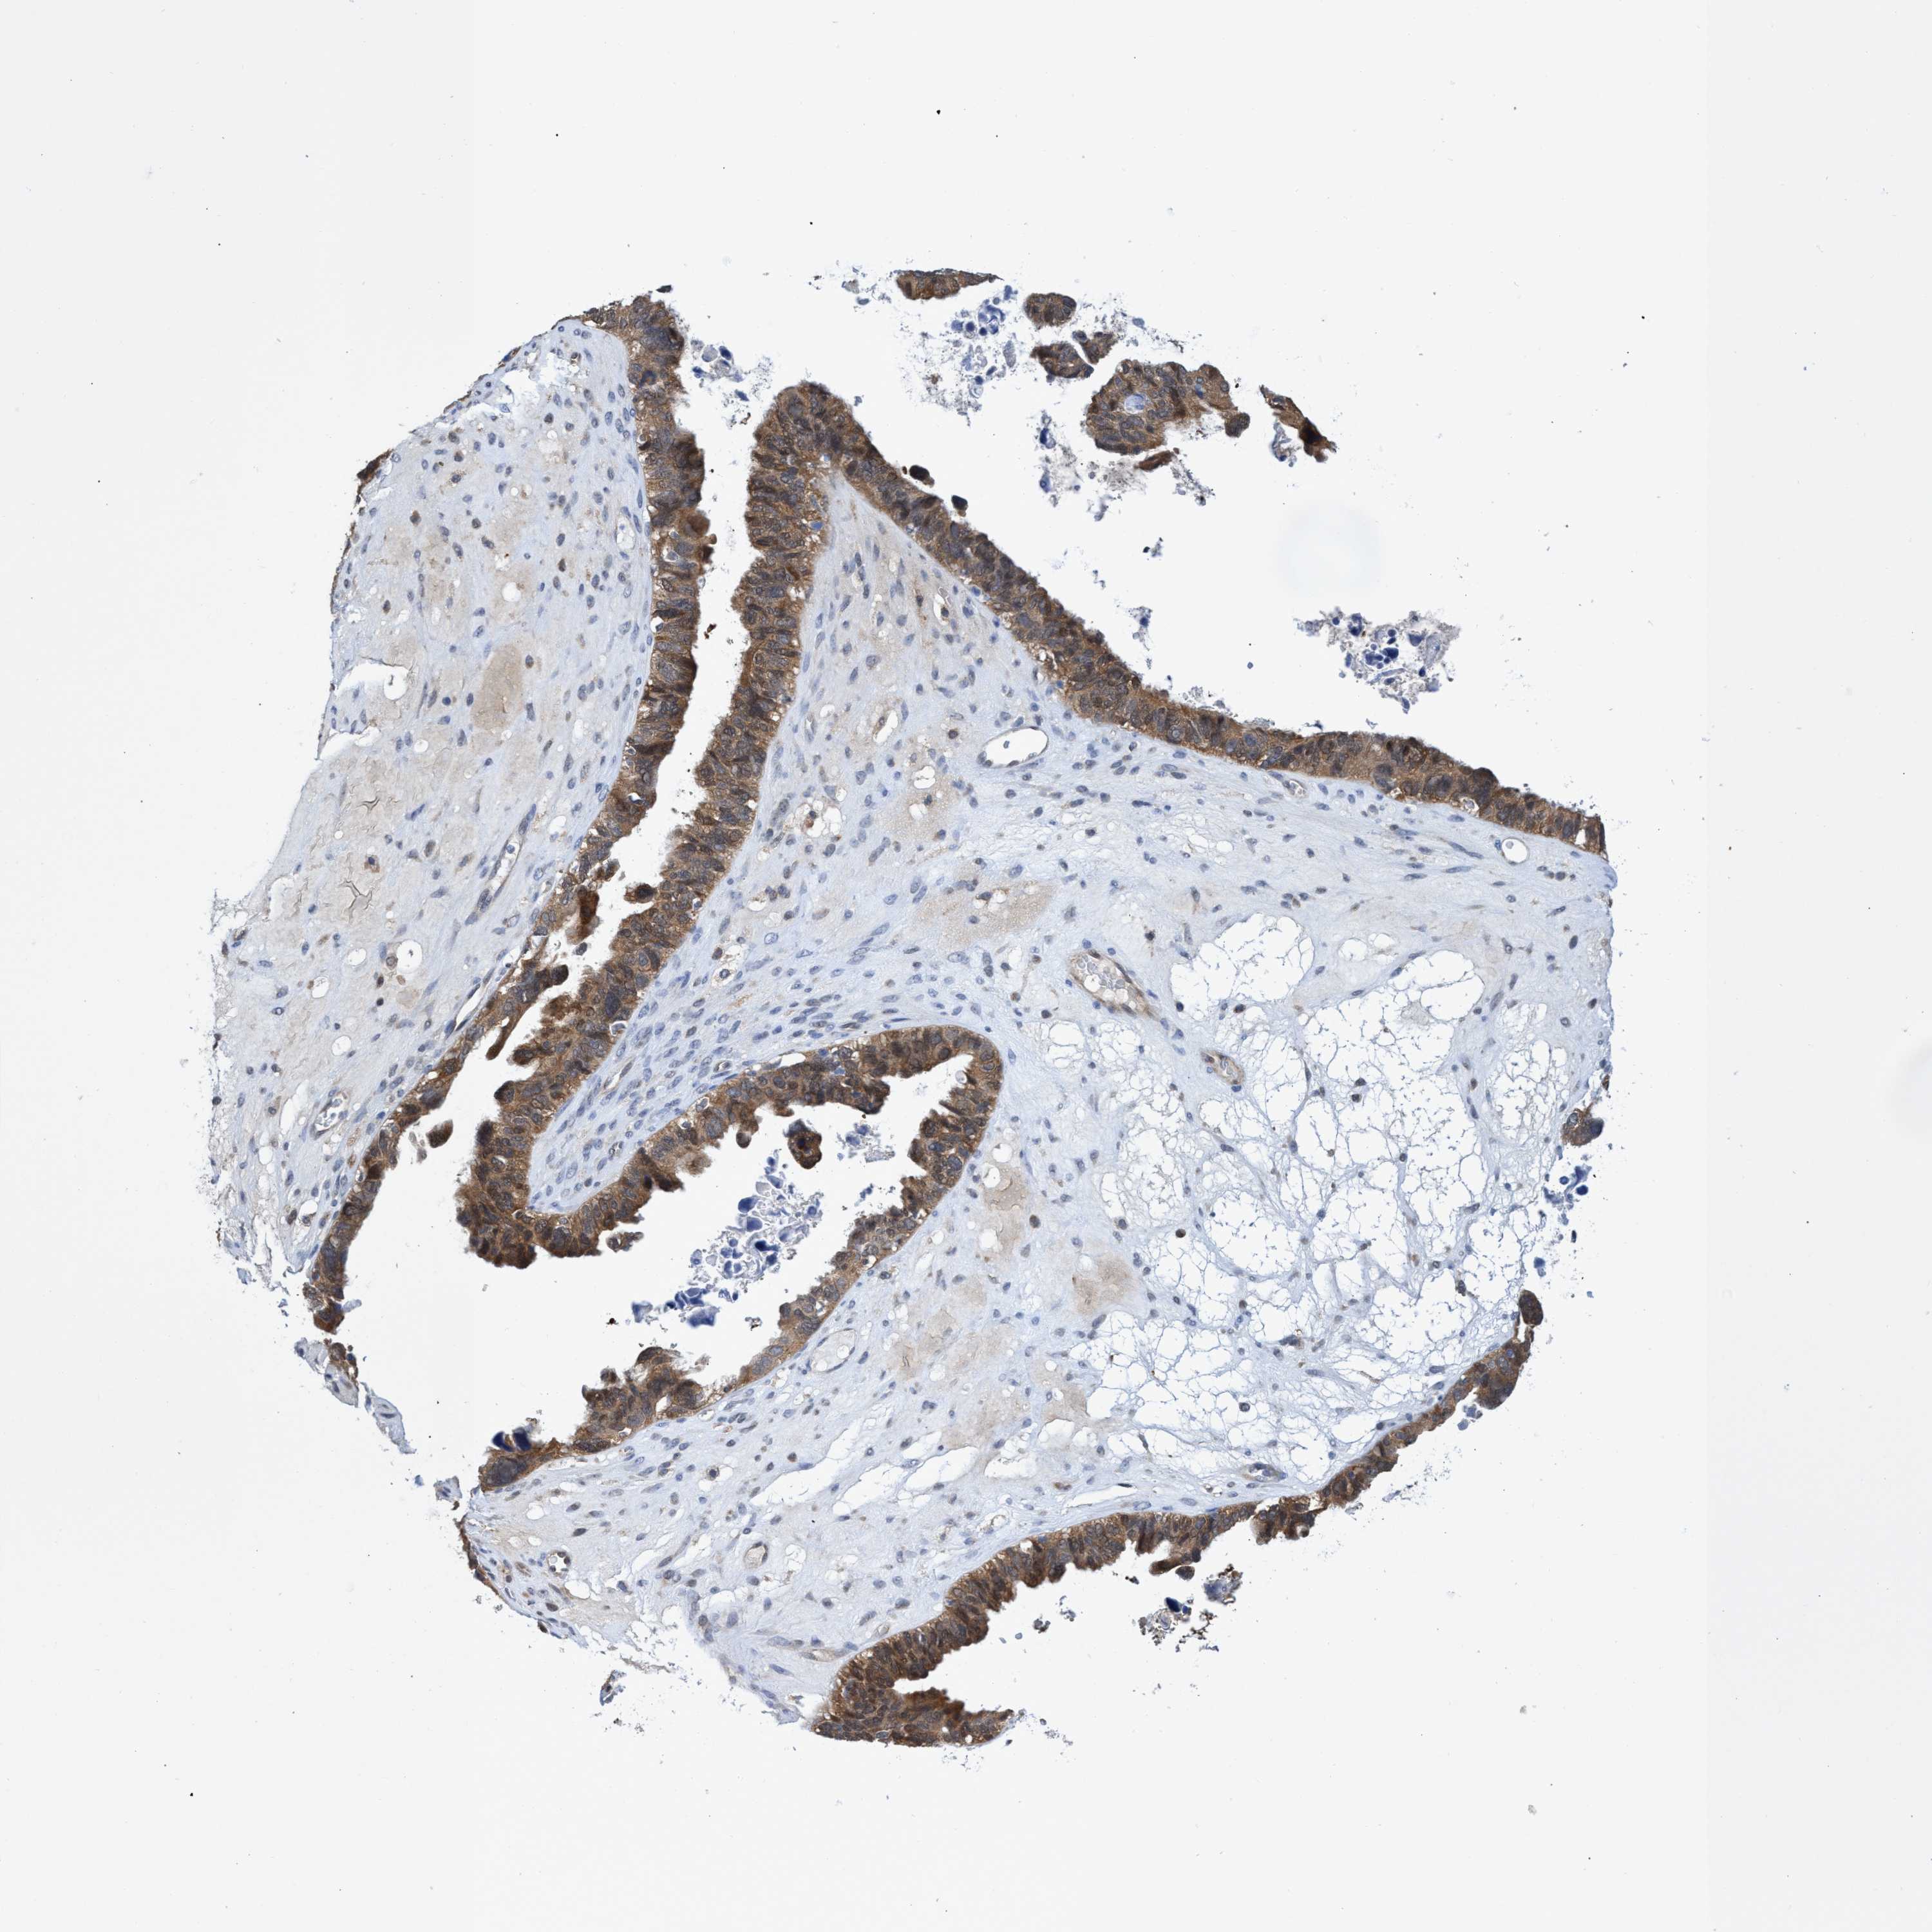

OVARIAN CANCER - Protein expressioni

A mouse-over function shows sample information and annotation data. Click on an image to view it in a full screen mode. Samples can be filtered based on level of antibody staining by selecting one or several of the following categories: high, medium, low and not detected. The assay and annotation is described here.

Note that samples used for immunohistochemistry by the Human Protein Atlas do not correspond to samples in the TCGA dataset.

Antibody stainingi

Antibody staining in the annotated cell types in the current human tissue is reported as not detected, low, medium, or high, based on conventional immunohistochemistry profiling in selected tissues. This score is based on the combination of the staining intensity and fraction of stained cells.

Each image is clickable and will lead to virtual microscopy that enables deeper exploration of all samples and also displays staining intensity scores, fraction scores and subcellular localization as well as patient and tissue information for each sample.

Antibody HPA023204

Antibody HPA027776

Staining

High

Medium

Low

Not detected

Intensity

Strong

Moderate

Weak

Negative

Quantity

>75%

75%-25%

<25%

None

Location

Nuclear

Cytoplasmic/membranous

Cytoplasmic/membranous,nuclear

Cystadenocarcinoma, serous, NOS

Carcinoma, endometroid

Cystadenocarcinoma, mucinous, NOS

Carcinoma, NOS